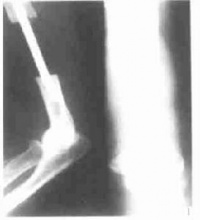

1.手术如果没有辅助治疗或病变对辅助治疗没有反应,则要获得可靠的局部控制就需要根治性外科切除

当病变对术前放疗和(或)术前化疗有反应时,则局部切除后局部复发率小于10%。对于位置深在的位于肢体近端和躯干周围的较大病变而言即使对辅助治疗有满意的反应,施行边缘切除后,局部复发率仍然非常高与此相比,那些位于肢体远端的小而表浅的病变对新辅助疗法反应满意者,局部复发风险较低。

滑膜肉瘤--外科处理影像

对Ⅰ期小肿瘤,广泛切除是肯定的治疗,其复发率不高,如一旦复发,则需广泛截肢常遇到的麻烦是在术前并未认识到是滑膜肉瘤,而作为腱鞘囊肿行囊内或边缘切除。术后已摸不到肿物无法确定其分期,待病理结果为肉瘤已将病变扩大到伤口的边缘。其处理办法是等待局部有了复发的证据再来设计手术方案此种办法的缺点是有转移的中等危险,并且其复发也比原来广泛,处理也被耽搁其变通的办法是对危险区行放射治疗以抑制未表现出来的复发用放疗的缺点是不能肯定手术时播散的范围,并且肿瘤细胞散在缺氧的瘢痕之中健疗效果更差。再者在手或足部放疗其放疗瘢痕使手或足功能更为障碍。再一个变通办法是在可能播散区的近侧行广泛截肢,此法增加了残废,但对控制疾病则是肯定的。 Ⅱ期肢体近侧大滑膜肉瘤需要彻底外科处理广泛切除或广泛截肢有较高的复发率,附加其他治疗,特别是在术前给予放射治疗使高度恶性的滑膜肉瘤行广泛切除后的复发率明显降低。至于更为保守的边缘切除并用附加放疗能否有如上述良好结果则尚无报道。附加治疗对此肿瘤效果较好,是由于滑膜肉瘤对放疗较其他软组织肉瘤更为敏感